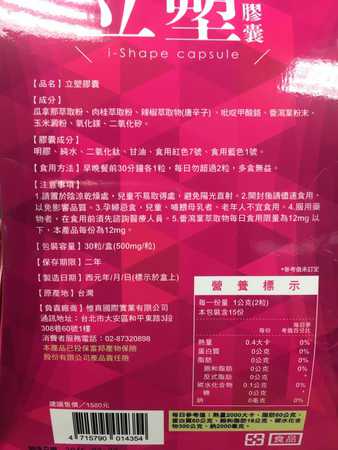

Supercut塑魔纖立塑膠囊的成分有:瓜拿那萃取粉、肉桂萃取粉、辣椒萃取物(唐辛子)、吡啶甲酸鉻、番瀉葉粉末、玉米澱粉、氧化鎂、二氧化矽。

之前上過相關課程,成分表是依照每項成分的多寡來排列順序,排在最前面的就是產品的主要成分!

那我就跟大家分享瓜拿那萃取粉、肉桂萃取粉和辣椒萃取物吧

瓜拿那萃取和辣椒萃取是可以幫助纖體瘦身常見的營養素!

1.「瓜拿那」是原產於亞馬遜流域的一種藤蔓植物,富含酵素可以幫助排便順暢,並且能抑制脂肪分解酵素,此外也有降低食慾的效果喔~~萃取物中含有天然咖啡因,可以提高新陳代謝率以及排出多餘水分!

2.「辣椒萃取物」則是可以幫助體內脂肪燃燒、增加卡路里的消耗,達到防止脂肪積聚的效果

3.「肉桂萃取物」看到肉桂,就想到麥當勞的蘋果派或是手掌麵包,雖然很多人很害怕那味道,但艾哥愛死肉桂了!!!!肉桂在古代被視為是最有價值的東方香料之ㄧ,中世紀時,肉桂的聲望僅次於昂貴的黑胡椒,除了香料和薰香價值, 傳統上肉也被用來治療消化不良、脹氣、關節疼痛、出血和經痛,研究也指出肉桂可以促進新陳代謝喔

食用方式:早晚餐前30分鐘各1粒,每日不超過2粒。(多食無益)

番瀉葉萃取物每日食用限量為12mg以下,